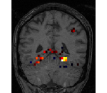

face

vs house

TV-l1

Graph-net

Social sparsity

Finally, an important aspect of the brain decoders is whether they segment well the brain regions that support the decoding. Such a question is hard to validate, yet there is evidence that TV- is a good approach [5]. Fig. 2 displays the decoder maps for the object-recognition tasks. For these tasks, we expect prediction to be driven by the functional areas of the visual cortex [27]. Indeed, the maps outline regions in known visual areas. The graph-net maps are much more scattered and less structured than the others. Conversely, the social sparsity maps are sparser and outline a smaller number of clusters.